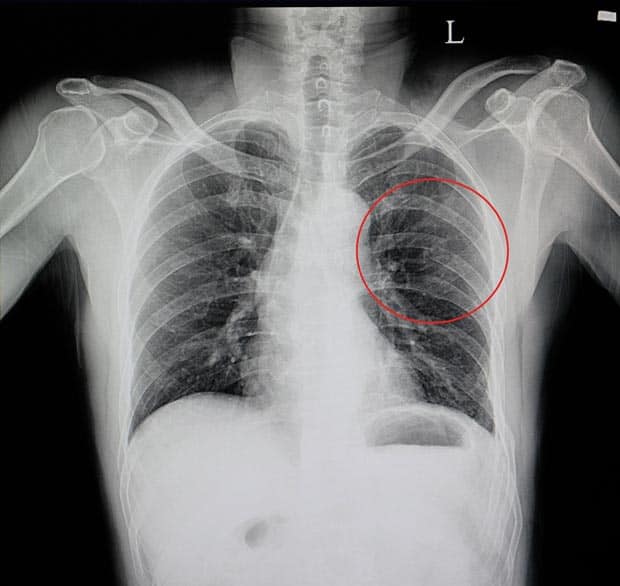

• Лучевые исследования. Рентгенография позволяет выявить участки инфильтрации легочной ткани в месте ушиба через несколько дней после травмы. Она необходима при подозрении на перелом ребер, пневмо- и гемоторакс. Компьютерная томография (КТ) рекомендуется при более тяжелых патологиях, таких как разрыв легкого, пневмоцеле и ателектазы.

Рентгенологическое исследование Рентгенография выявляет затемнения в поврежденных тканях и позволяет судить о наличии гематом в легких. Ушиб может привести к кистозным образованиям, заполненным воздухом. Рентгенологические признаки травмы могут проявляться не сразу, поэтому рекомендуется компьютерная томография, которая дает более детализированное изображение повреждений.